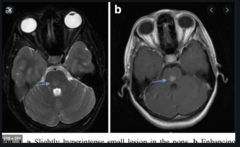

capillary telangiectasia

Made of single walled endothelium. abnormal collection of enlarged capillaries WITH intervening normal brain tissue (unlike cavernous hemangioma) DONT bleed Most commonly a single lesion in the pons BEST seen on gradient echo (slow flow with DEoxyhemoglobin) Can occur after radiation therapy No smooth muscle/elastic fibers. Intervening brain is usually normal.